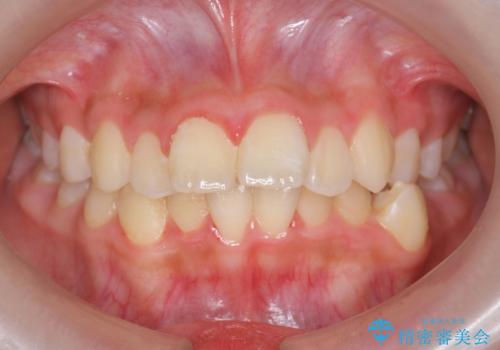

中学生のマウスピース矯正 歯を抜かずにキレイに

- 出っ歯を主訴に来院。

非抜歯ながらも、矯正用のインプラントを使用し、出来るだけ前歯を下げるように工夫して治療しました。

治療結果にはお母様、ご本人も含め、大変喜んでいただきました。

歯を抜かずに治療しましたが、治療前後で口元が悪化しないように治療することができました。